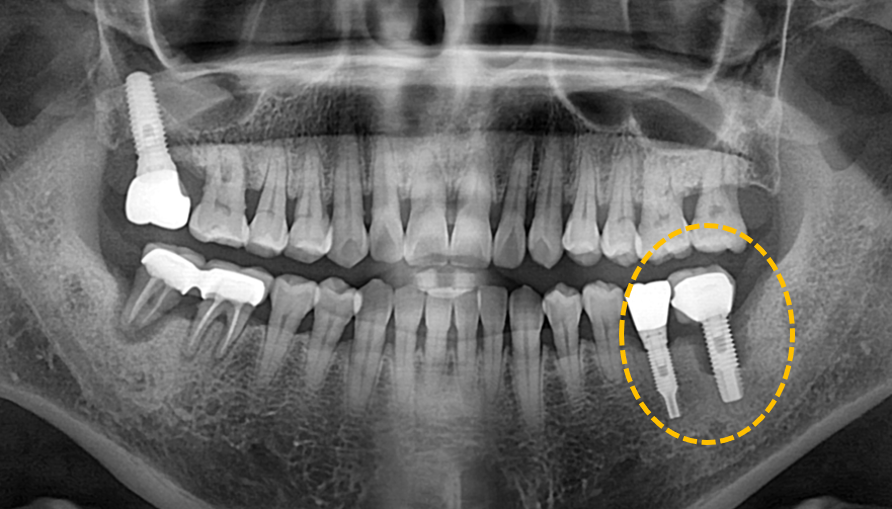

실패한 임플란트 재치료

Before

타원에서 식립한 임플란트에 염증이 생겨 임플란트 뿌리의 60% 이상 치조골 소실이 나타난 상황이었습니다.